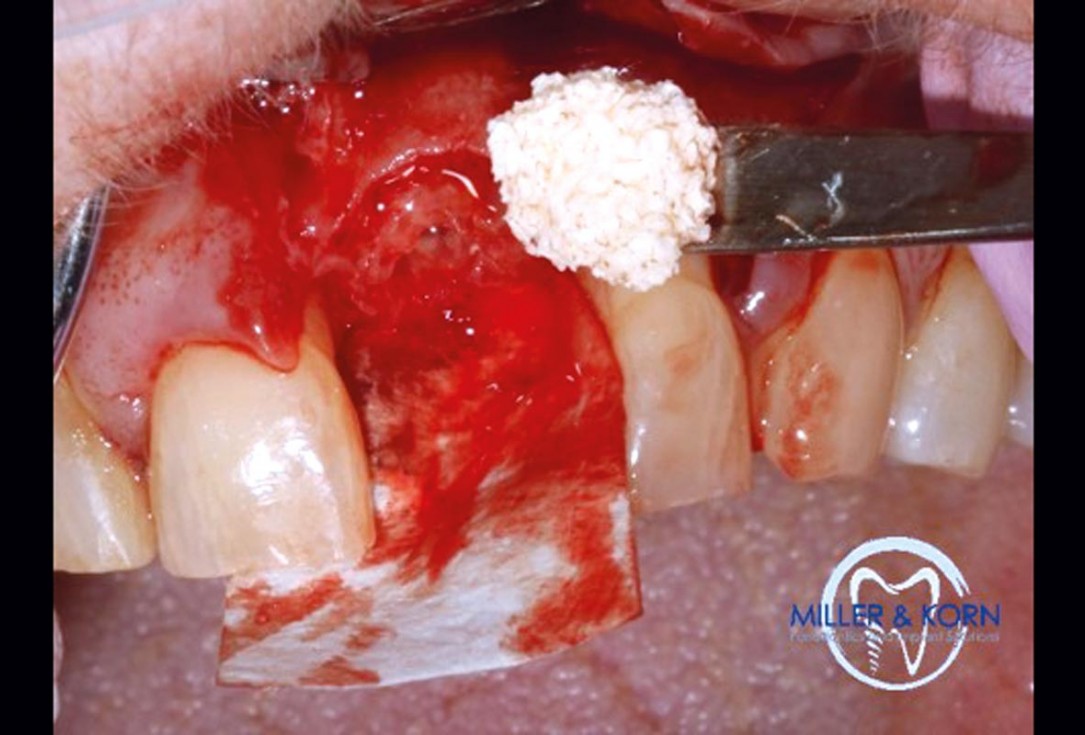

25/39 - Application of cerabone®Immediate implant placement and correction of horizontal and vertical bone loss using an allograft bone ring, cerabone® and Jason® membrane - Drs. Miller and Korn

-